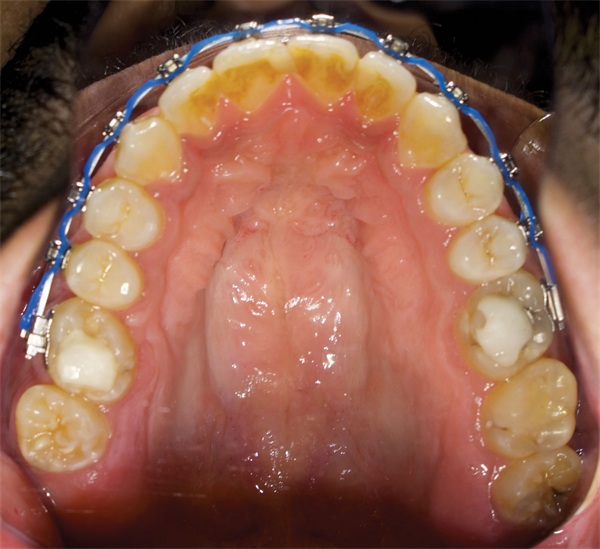

The cephalometric findings pointed clearly toward vertical maxillary excess. The asymmetric molar relationships, increased lower facial height, and posterior crossbite tendency all reinforced a picture that self-ligating brackets and wire changes were never going to resolve. The community’s response was equally clear: The ideal treatment is orthognathic surgery. The harder question was what to do when surgery is not a viable option (Figs. 1–10).

Fig. 3

Before any treatment planning conversation could move forward, one Townie raised a foundational concern: The incoming records may not yet be sufficient. Working with mounted casts was suggested as a prerequisite given the complexity of the case. The asymmetric molar relationships and transverse discrepancy made it difficult to fully assess arch coordination from photographs and radiographs alone.

When surgery is off the table because of cost or access, the discussion must shift to what camouflage could realistically accomplish. TADs for posterior intrusion came up consistently, with several orthodontists noting that the bite turbos placed during the original treatment had likely allowed further posterior eruption, compounding the open bite. Myofunctional therapy was recommended to address tongue posture as a contributing factor. Wisdom tooth removal was suggested to make intrusion and potential distalization more manageable. One Townie offered a more conservative read: banding the upper second molars and repositioning the upper first molars buccally to improve posterior occlusion, or trialing a posterior bite plate for molar intrusion as a lower-intervention option. Several orthodontists cut straight to it and recommended removing the brackets entirely, allowing a rest period, taking fresh records, and replanning the case from the beginning before any active treatment resumed.